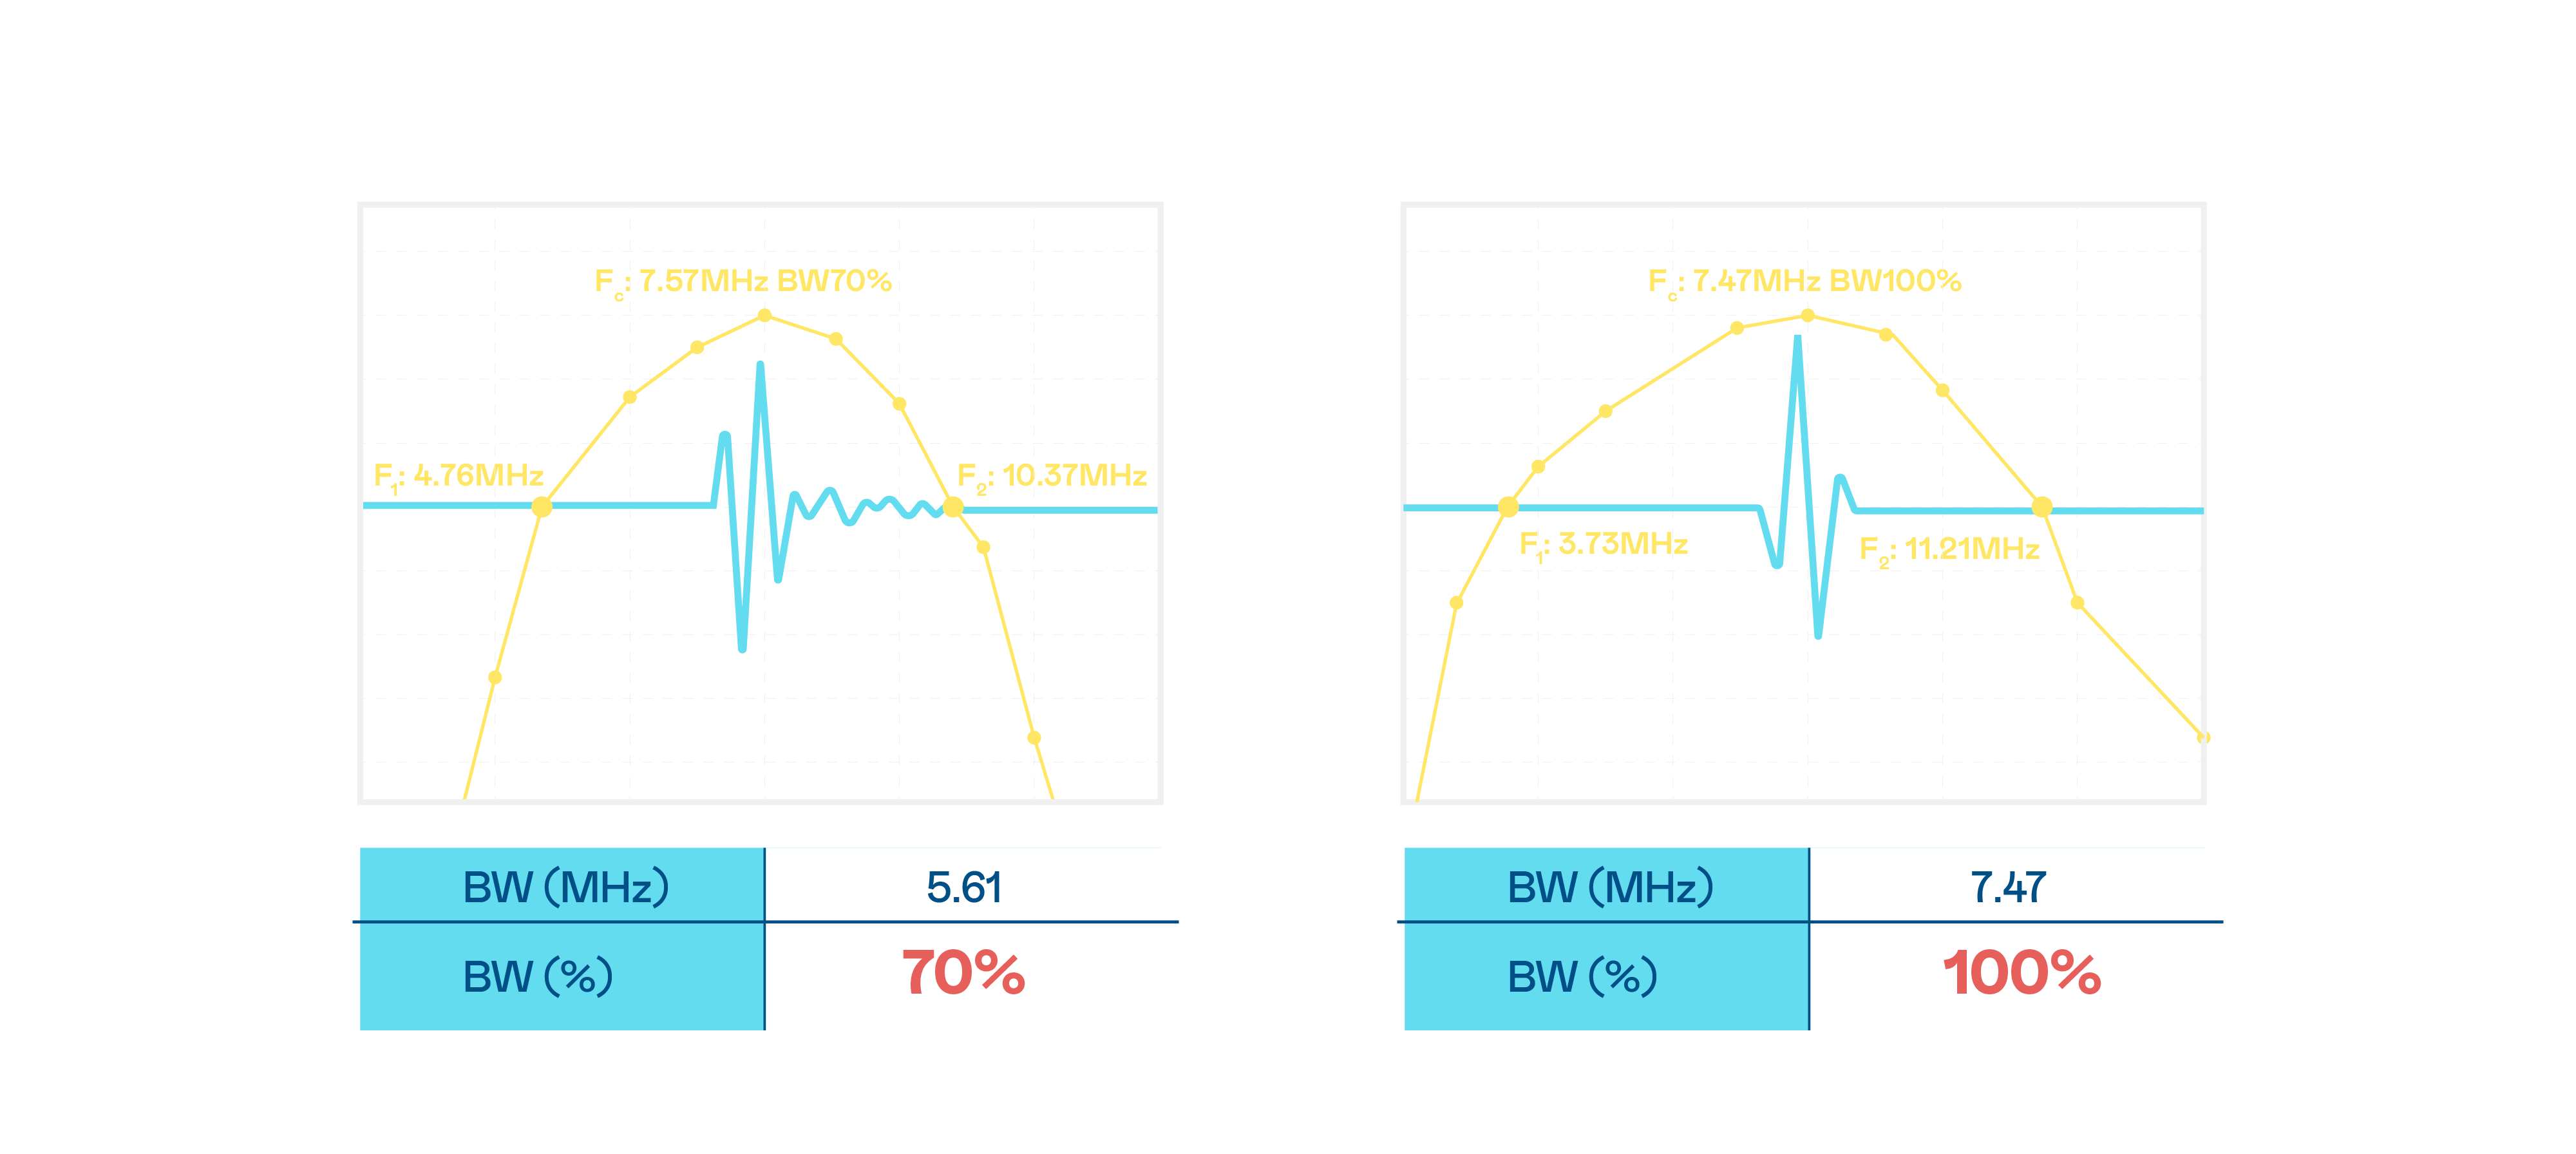

CMUT 技術是一種用電容式微機電元件來產生超音波訊號的技術。與傳統 PZT 壓電式技術相比,CMUT 頻寬增加 30%,更寬頻的超音波訊號讓影像解析度大幅提升,是實現高影像品質醫療超音波掃描、促進精準醫療發展的關鍵技術。

大頻寬帶來超清晰影像

超音波影像的解析度高低,首先取決於探頭能發出的訊號頻寬。AG百家乐 CMUT 可提供高清晰的超音波訊號,提供高頻寬、高靈敏度、影像紋理細節更高的超音波影像,協助醫護人員縮短影像判讀時間及利用精準的醫療影像進行診斷。